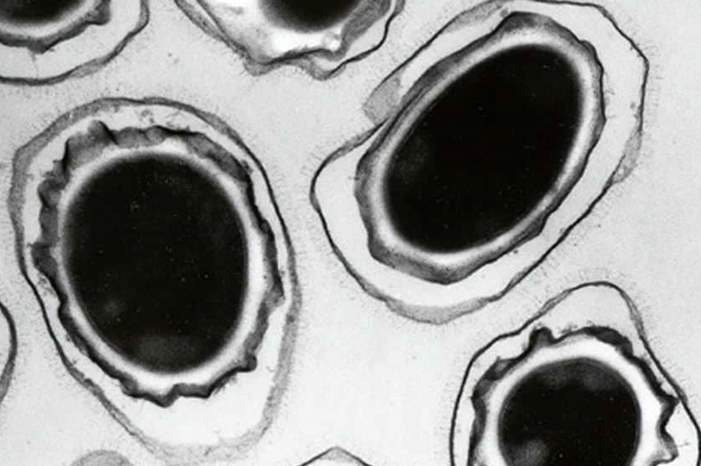

قال مسؤولون في مجال الصحة إنه لا يوجد مؤشر على تباطؤ انتشار البكتيريا الخارقة، أي المقاومة للمضادات الحيوية، في أوروبا، مما قد يزيد صعوبة علاج التسمم الغذائي وغيره من أشكال العدوى.

وتتطور المقاومة للدواء بفعل إساءة استخدام المضادات الحيوية وغيرها من الأدوية المضادة للميكروبات، أو الإفراط في استخدامها، الأمر الذي يشجع البكتيريا على التطور من أجل البقاء بإيجاد طرق جديدة للتغلب على الدواء.

وخلص التقرير إلى أن مقاومة بكتيريا تعرف باسم "كامبيلوباكتر"، ويمكن أن تصيب الإنسان بالتسمم الغذائي، لأحد المضادات الحيوية شديدة في بعض الدول، لدرجة أن هذه الأدوية لم تعد فعالة في علاج الحالات الخطيرة.

وأضاف التقرير أن معظم الدول قالت إن مقاومة بكتيريا "سالمونيلا" التي تصيب البشر للمضاد الحيوي "فلوروكينولونيز" تزداد، كما أن مقاومة 3 أو أكثر من مضادات الميكروبات شديدة في بكتيريا "سالمونيلا" التي تصيب البشر والحيوانات.